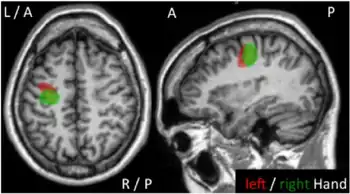

Epilepsia partialis continua is a rare[1] type of brain disorder in which a patient experiences recurrent motor epileptic seizures that are focal (hands and face), and recur every few seconds or minutes for extended periods (days to years).